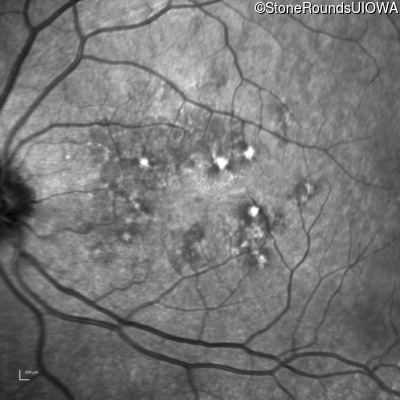

Infrared Fundus Photograph - Left - 20/20

Exemplar